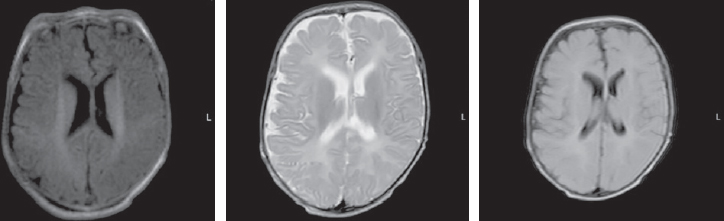

The child’s condition remained critical, with impaired consciousness, extension contractures in the elbow and knee joints, and non-epileptic paroxysmal states, such as bronchospasm and apnea persisting. Startle reflexes were pronounced and with any tactile stimulation, startle (generalized myoclonus) was registered. With the progression of neurological disorders, an increase in the cystic-atrophic changes was noted and hydrocephalus was formed. The data of MRI over a time, performed at the age of four months, are presented in Fig. 3.

Fig. 3. Magnetic resonance imaging of a patient at the age of 4 months. Axial sections, T1 VI, T2 VI, Flair. There is a negative dynamics in the form of cystic-atrophic changes in the large hemispheres of the brain with the formation of atrophic hydrocephalus. The appearance of symmetrical subshell clusters in the form of subdural hygromas

Рис. 3. Магнитно-резонансная томограмма пациента в возрасте 4 мес. Аксиальные срезы, Т1ВИ, Т2 ВИ, Flair. Наблюдается отрицательная динамика в виде кистозно-атрофических изменений в больших полушариях головного мозга с формированием атрофической гидроцефалии. Появление симметричных подоболочечных скоплений в виде субдуральных гигром